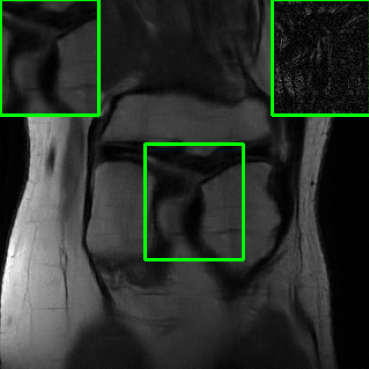

Results for the FastMRI Knee Dataset: In Fig 5 and Fig 7, we report PSNR and SSIM results of different methods at two sampling acceleration factors for the knee dataset. Therein, we observe quite similar outcomes to those reported in Fig 3. Figs. 6 and 8 show reconstructed images by different methods for knee scans at 4x and 8x undersampling, respectively. We observe that SMUG and Weighted SMUG show fewer artifacts, sharper features, and fewer errors when compared to Vanilla MoDL and other baselines in the presence of the worst-case perturbations.

Results on Adversarial Perturbation Strength: In Fig. 9 presents average PSNR results over the test dataset for the considered models under different levels of worst-case perturbations (i.e., attack strength ). We used the knee dataset for this experiment. We observe that SMUG and weighted SMUG outperform RS-E2E, vanilla MoDL, and Deep-Eq across all perturbation strengths. When compared to Score-MRI and AT, our proposed methods consistently maintain higher PSNR values for moderate to large perturbations (less than ). For instance, when , weighted SMUG reports more than 1 dB improvement over AT and Score-MRI.